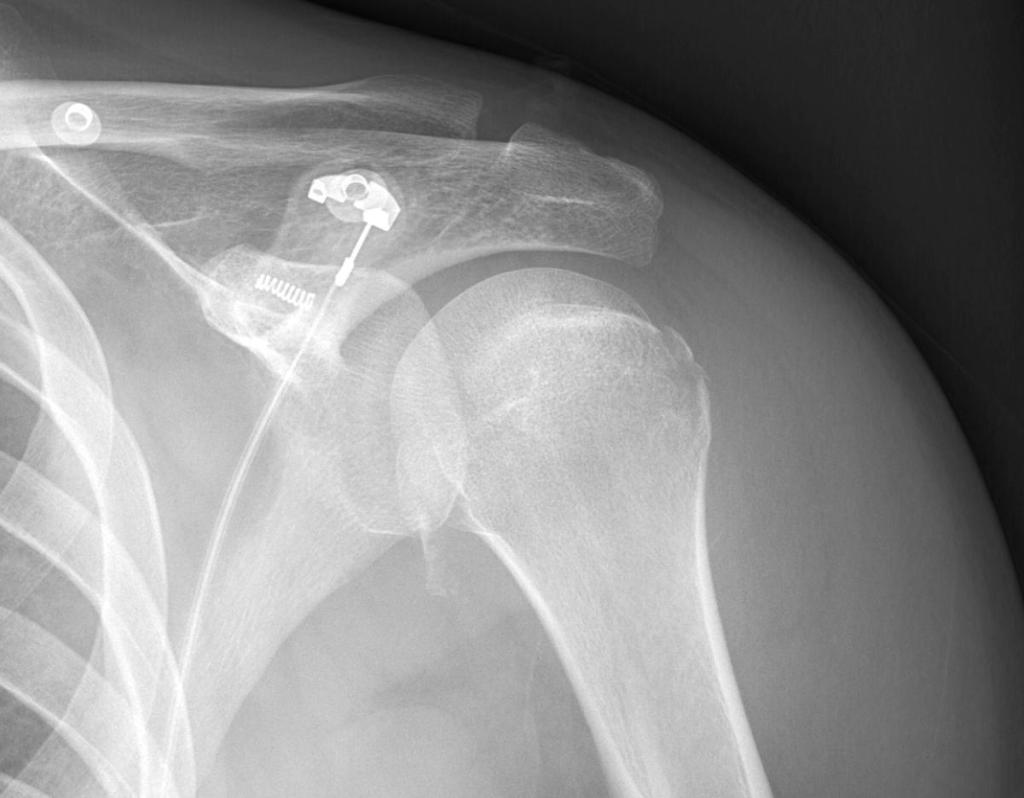

Een 25-jarige man werd gezien op de Spoedeisende Hulp vanwege een forse zwelling van de linker schouder na een epileptisch insult. Patiënt kon niet bevestigen of er een luxatie was geweest. Lichamelijk onderzoek was beperkt uitvoerbaar als gevolg van de zwelling en de pijn.

Wat is uw diagnose?